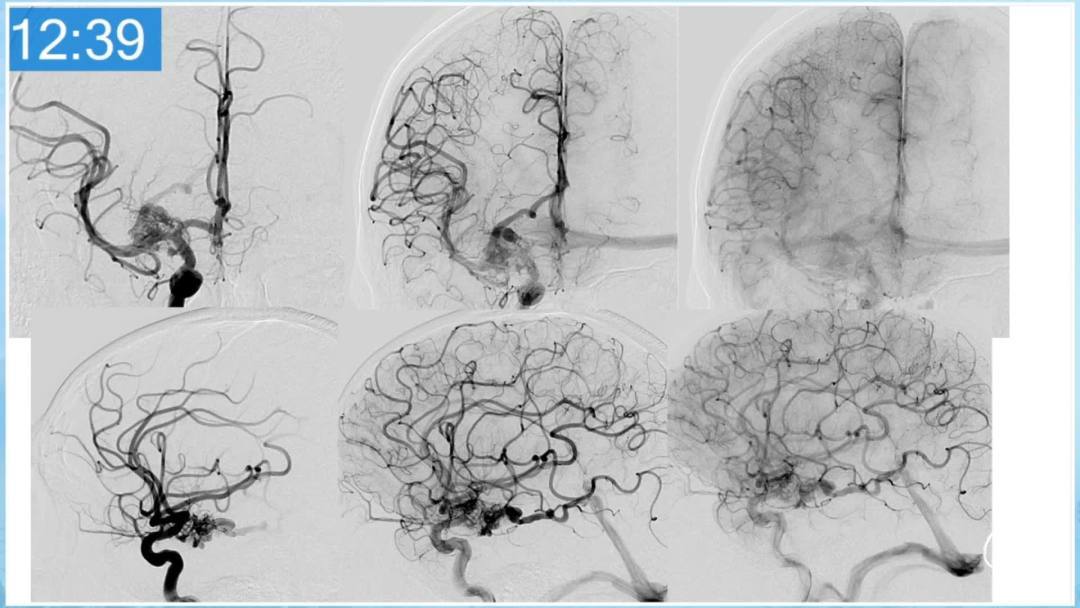

合理的复合平台下的综合治疗,针对每一个病变对应不同方法安全性分析,不预设、不排斥,每种技术发挥到最佳,互相保障。

本期为大家特别分享:空军军医大学唐都医院邓剑平教授的精彩会议内容《颅内动静脉畸形的复合手术治疗》,欢迎大家阅读和分享!